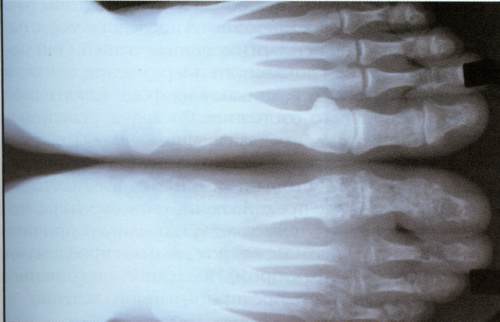

Параартикулярный несимметричный остеопороз, сужение суставных щелей, эрозивная деструкция костей устанавливаются по рентгенографическим снимкам. Чаще всего дегенеративным изменениям подвергаются стопы, тела позвонков. У трети пациентов диагностируется воспаление крестцово-подвздошных сочленений.